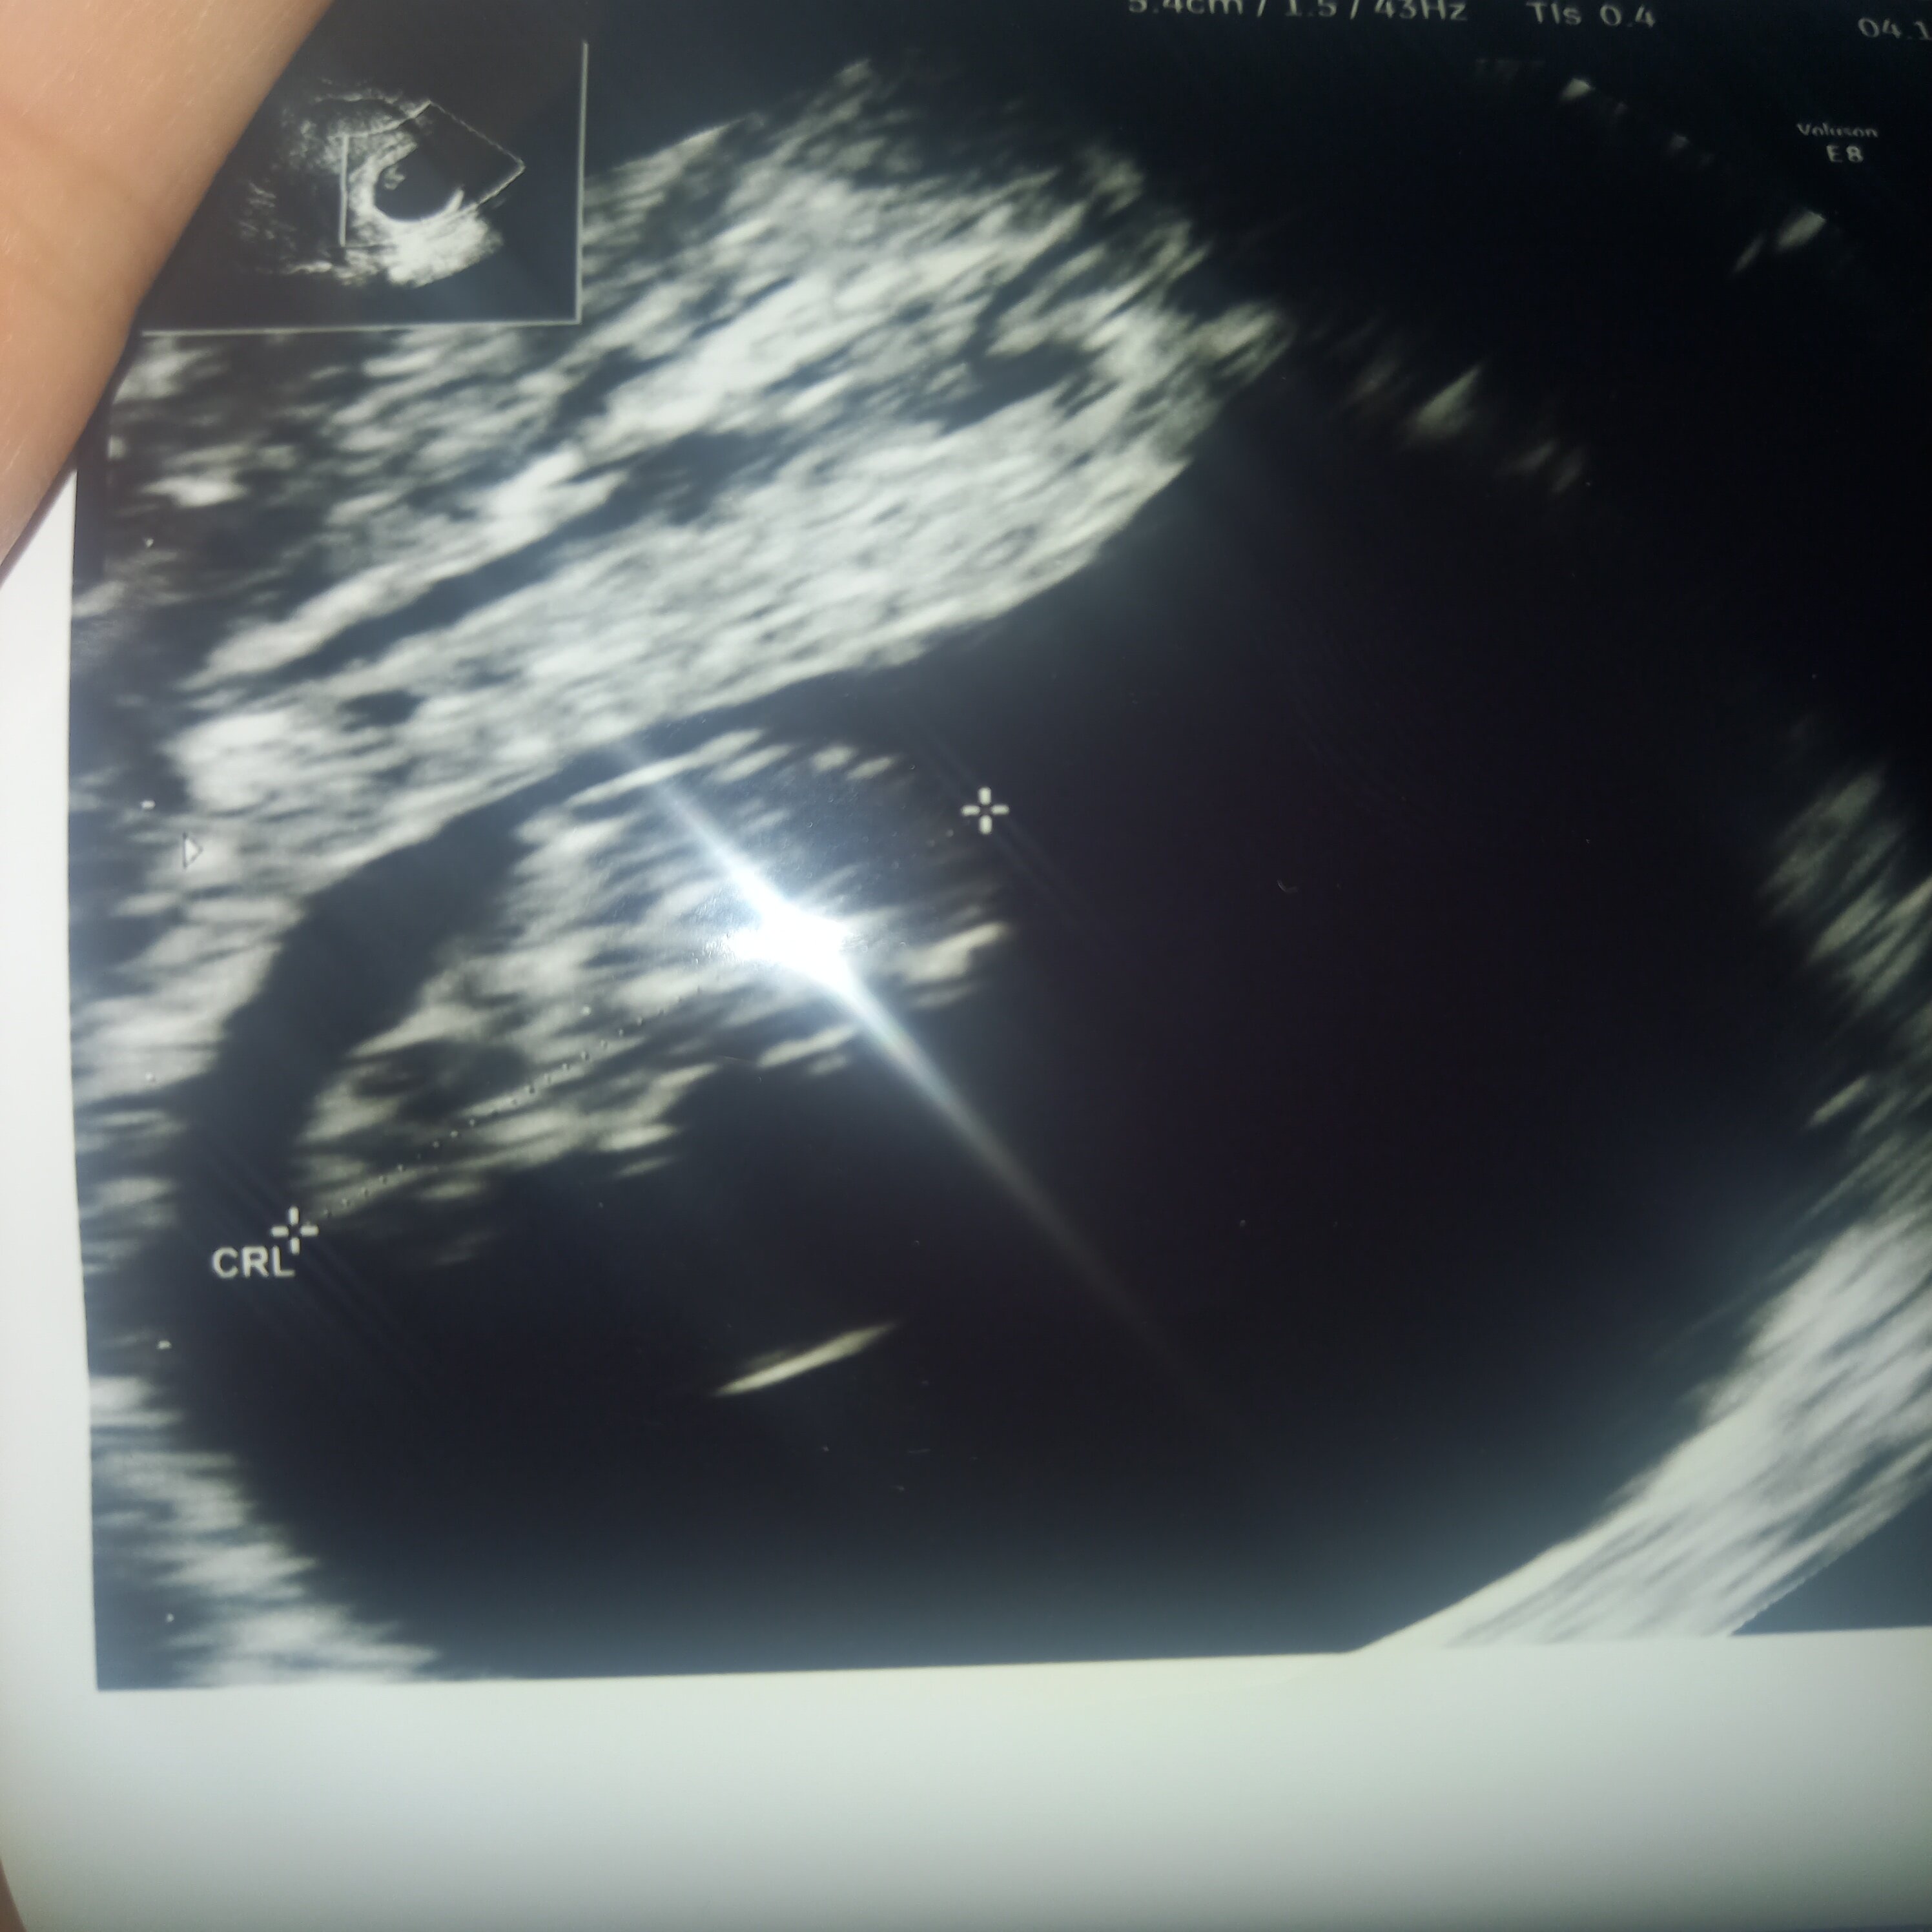

jest dzidzia, jest serduszko. Z USG wychodzi 7+6 a z om jest 8+1. Zarodeczek 1,49 wygląd kurczaczka. Serducho 134/min.